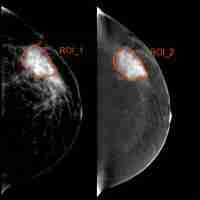

| Abstract | Objective To develop and validate a radiomics nomogram based on pre-treatment, early treatment ultrasound (US) radiomics features combined with clinical characteristics for early predicting response to neoadjuvant chemotherapy (NAC) in breast cancer. Method A total of 217 patients with histological results of breast cancer receiving NAC 4-8 cycles before surgery were enrolled from January 2018 to December 2020. Patients from the study population were randomly separated into a training set(n=152) and a validation set(n=65) with a ratio of 7:3. A total of 788 radiomics features were extracted from each region of interest in US image at pre-treatment baseline (radiomic signature, RS1) , early treatment (after completion of the two cycle of NAC, RS2) and Delta-radiomics (calculated between the pre-treatment and post-treatment features, Delta RS). The Max-Relevance and Min-Redundancy (mRMR) and the least absolute shrinkage and selection operator (LASSO) regression were applied for feature selection. The predictive nomogram was built based on the radiomics signature combined with clinicopathological risk factors. Discrimination, calibration and prediction performance was further evaluated in the validation set. Result Of 217 breast masses, 127 (58.5 %) were response to NAC and 90 (41.5 %) were non-response to NAC. Following the features selection, 9 features in RS1, 11 features in RS2 and 8 features in Delta RS were remained, respectively. With multivariate analysis, the RS1, RS2, Delta RS and Ki-67 expression were independently associated with breast NAC response. But the performance of the Delta RS (AUCDelta RS =0.743) was not higher than the RS1 (AUCRS1=0.722, PDelta vs RS1 =0.086) and RS2 (AUCRS2=0.811, PDelta vs RS2 =0.173) with the delong test. The nomogram incorporating RS1, RS2 and Ki-67 expression showed better predictive ability for NAC response with an area under the curve (AUC) of 0.866 in validation cohorts than either the single RS1 (AUC 0.725) or RS2 (AUC 0.793) or the Ki-67 (AUC 0.643). Conclusion The nomogram incorporating pre-treatment and early-treatment US radiomics features and Ki-67 expression had good performance for NAC response in breast cancer, which could provide valuable information for individual treatment and timely adjustment of chemotherapy regimens. |